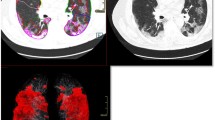

In terms of lung changes, the appearance of different types of lung is shown in Fig. 4. CT scans showed that 298 (12%), 778 (32%) and 1300 (53%) patients had pure GGO, GGO with sub-solid lesions and all three types, respectively. There were 2305 patients (94%) and 71 patients (3%) primarily presenting with GGO and sub-solid lesions, respectively (Table 2). As demonstrated in Table 3, the distribution of CT scan signs was not significantly different between male or female patients (p = 0.4125). However, elderly patients (≥ 60 years) were more likely to develop pneumonia and manifest with sub-solid lesions in CT scans compared to younger patients (p < 0.001) (Table 4).

Representative CT scans of the different lesions observed in patients with COVID-19 pneumonia. A A 52-year-old man. CT image showing ground glass opacity lesions in both the upper lung fields. B A 46-year-old woman. CT image showing ground glass opacity lesions mixed with sub-solid lesions in both the lower lung fields. C A 35-year-old woman. CT image showing solid lesions in the right lower lung fields